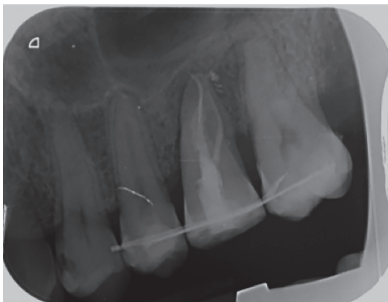

In the radiograph examination, through a panoramic radiograph, both lower third molars were seen retained in horizontal position (Figure 3), and apical radiolucent images in positions of 2.6 and 4.6. The cone beam scan evaluated the root morphology of the left upper third molar and the size of the apical radiolucent lesion of the left upper first molar (Figure 4), necessary data to assess the degree of adaptation of the donor tooth in the recipient bed.

associated with the root remains of 2.6 and the conical root of 2.8 are seen.